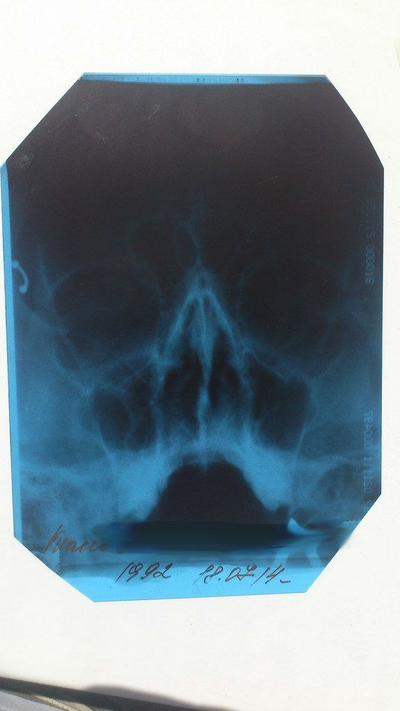

-- Понятно, почему она не дышит. -- сказал ЛОР заглянув в ту ноздрю, которая у меня хоть как-то дышит. Выяснилось, что моя перегородка искривлена так, что усложняет дыхание обеими ноздрями.

Это была моя норма жизни. Во сне и во время физических нагрузок всегда дышал ртом. На операцию я решился благодаря брату, который её сделал годом раньше. С его слов, ничего страшного и почти бесплатно. Погуглив я узнал, что кривая носовая перегородка может быть причиной большого списка последствия. Эх, была не была!

Бесплатно делают там же, где платно, поэтому я выбрал первый вариант. Обычный ЛОР по ОМС даёт направление на КТ и на предоперационную комиссию. Чтобы ускорить, я пошёл на платную комиссию за 3 т.р. Операция была назначена через 2 месяца. Платная за 100 т.р. тоже не раньше.